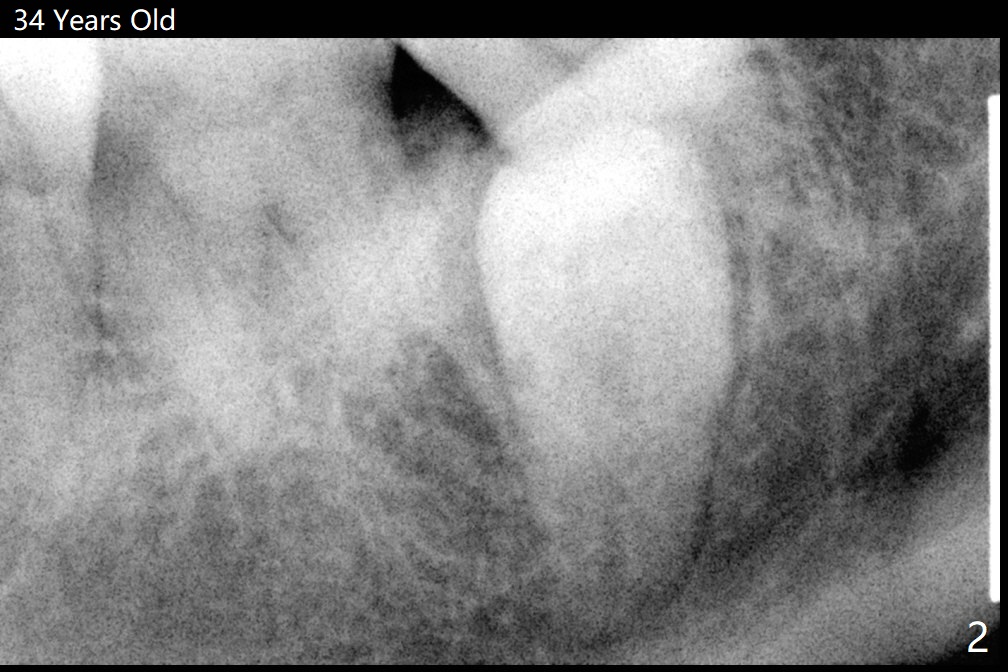

Root Resorption Associated with Supernumerary Tooth

A 34-year-old woman has 2 supernumerary lower 2nd premolars located between the 1st and 2nd molars (Fig.1,2). Ten years later, the lower left 2nd molar has mobility associated with root resorption (Fig.3).